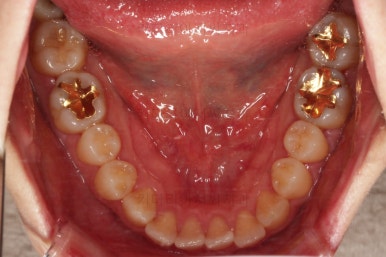

장치를 부착한 모습 참고해 주시고요.

아랫니는 중앙선을 맞추기 위해서 미니스크류를 이용해 한 쪽으로 당기는 중이고요.

이 과정에서 아랫니들이 약간은 뒤로 들어가져서 아랫입술 부위의 돌출감을 아주 약간은 줄일 수 있습니다.

윗니 임플란트 할 자리는 적절히 계속 맞춰줍니다.

중앙선도 점점 맞아지고 있어요.

임플란트 할 공간도 여유롭게 마련이 되었네요.